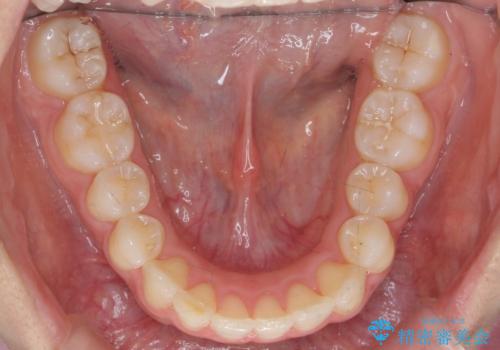

- 前歯のがたつきと突出を主訴に来院。

歯を抜かずに非抜歯で治療しました。